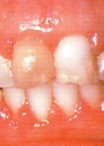

牙龈炎是由细菌的入侵造成的,表现为牙龈出血红肿,胀痛,继续发展侵犯硬组织,产生牙周炎症。

患有牙龈炎,齿龈会红肿,或有出血现象。若刷牙时发觉牙齿容易出血,或牙齿有触痛情况,便需要看牙科医生。

轻度的慢性单纯性牙龈炎所侵犯的是游高龈和龈乳头,严重者可侵犯附着龈、前牙区,尤以下颌前牙炎症明显。咬水果或刷牙时,牙龈出血。健康的牙龈即使用力刷牙,不会发生出血。正常的游离龈是很薄且紧贴牙面,牙龈有炎症时,龈缘充血发红、肿胀、松软,龈缘变厚,牙间乳头变为钝圆,与牙面不紧贴,而且龈沟加深,严重者附着龈可因组织水肿,点彩消失,表面光亮,龈缘可有糜烂或肉芽增生龈袋溢脓。龈炎进一步发展,牙龈大量毛细血管增生扩张、高度充血,大量炎症细胞组织液渗出,导致牙龈肥大,可覆盖部分牙冠,此时牙龈呈深红或暗红,探诊极易出血。病程较长者,可导致牙龈纤维增殖牙龈增生突起,此时牙龈颜色轻度发红或接近正常,质地较硬,出血较少。